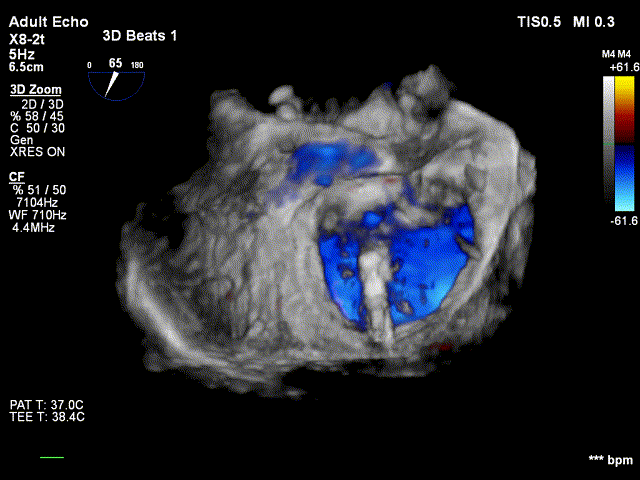

全麻后,首先在心前区的肋间切开3-4CM小切口,暴露心脏的心尖位置,心尖穿刺后进入导丝,利用导丝交换导管鞘完成通路建立。将系统送入左心房,顺利到达二尖瓣病变区域。在经食道超声引导下,术者通过反复评估二尖瓣反流位置、抓捕位置、反流程度,在2区主动脉瓣与二尖瓣闭合线垂直进行巧妙夹合,最终植入一枚ValveClamp®MVC-Ⅲf夹。超声评估夹子固定良好,组织桥完整,无葫芦征,位置、轴向均符合预期。患者术后反流程度从大量转至少量,手术取得圆满成功。患者恢复良好,已经顺利出院。

反流得到明显改善 术后3D动图